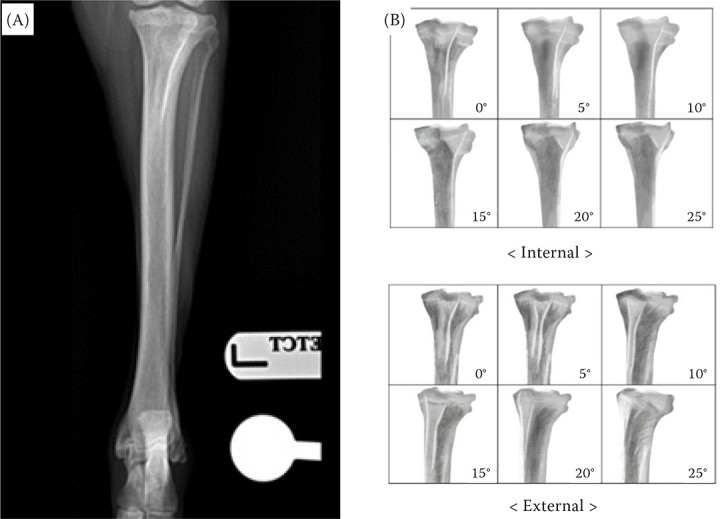

Tibial torsion assessment is crucial for understanding deformities and malalignments that can lead to joint pathologies in dogs. Different methods such as radiography, computed tomography (CT), and three-dimensional (3D) volume-rendering techniques have been employed to measure tibial torsion. This study compared the accuracy and reliability of tibial torsion angle (TTa) measurements obtained using radiography and ultrasound tilting techniques against those obtained using the 3D volume-rendering method in small-to-medium-sized non-chondrodystrophic dogs. Seven dogs with 11 hind limbs were included in this study. Descriptive statistics revealed mean TTa values for radiography (1.6° ± 5.14°), ultrasound (2.92° ± 3.98°), CT (4.57° ± 3.44°), and 3D volume-rendering method (5.29° ± 3.30°). Intraclass correlation coefficient (ICC) analysis indicated excellent intra- and interobserver agreement between the radiography and ultrasound methods. Correlation analysis showed positive correlations between all the methods. These findings demonstrate that radiography and the ultrasound tilting technique are reliable alternatives for measuring TTa. Although slightly lower ICC values were observed than those of the 3D volume-rendering technique, the radiography and ultrasound methods still exhibited good to excellent reliability, suggesting that these alternative methods could be effective diagnostic tools for assessing TTa in clinical settings with high accuracy and reliability.